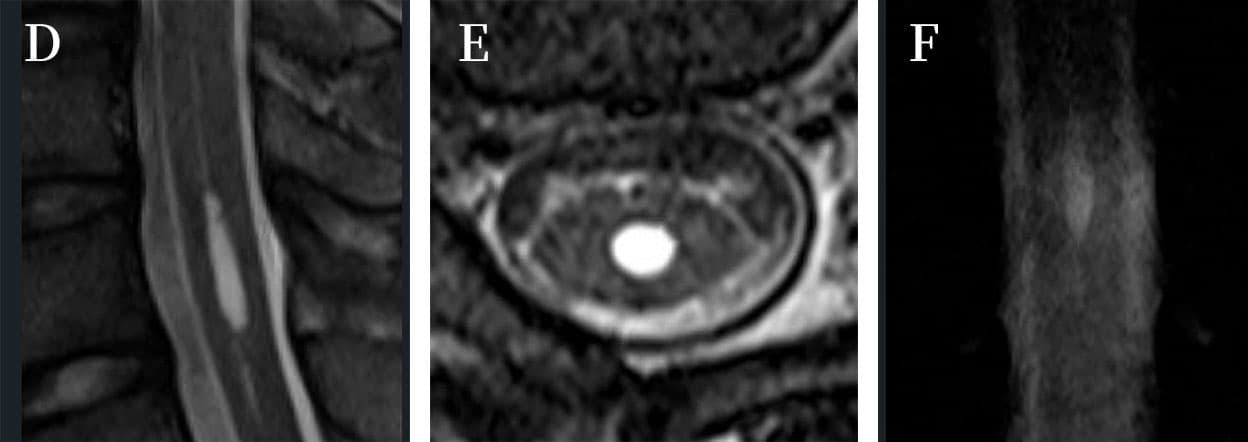

初診時はspecificな疾患を想起できなかったが、脊髄関連疾患ではないかと当たりをつけてorderしたMRI検査では脊髄空洞症が見つかった(写真B、C)。そうであれば、患者が図に示した違和感の変化は、中心管が開いて空洞が拡大する際に起きた変化ではないかと推察した。

胸背部の赤い皮膚変化(写真A)についてPubMed検索をしてみたが、該当する文献は見つからなかった。この皮疹は1週間もするときれいに消失してしまったので、おそらく超早期にしか見られないものだったのだろう、局所の循環に影響を与えた自律神経の異常を反映していたのかもしれない。貴重な症例なので英語文献に残そうかと思って原稿を書いてみたが、どのジャーナルに載せたら良いか迷っているところだ。

Vanishing skin rash of syringomyelia 「脊髄空洞症に見られた消える皮疹」

3weeks before coming into my clinic, she felt something pulling and a kind of numbness as well on her right lateral chest. Because it was not severe, she was just watching the symptoms. 2weeks after the initial sign began, not only the symptoms remained but also pain was coming out, she saw an orthopedist, but nothing was able to find out. The same morning that I saw her at my clinic, a skin rash had appeared on her right lateral chest and was located the Th2 area of the dermatome. She was seen in a dermatologist, but the doctor told her nothing, but herpes zoster was excluded. She wanted to know what happened to her, so I examined her in detail and ordered spinal MRI.

On the MRI findings, syringomyelia was on the level of Th2. I recognized that symptoms of abnormal feeling on her right lateral chest, skin rash as well were exceedingly early symptoms of syringomyelia. The rash had vanished in a week. I have not experienced before like this phenomenon. There were no articles I can find out if searching on the PubMed. So, if you see the patient at the chronic phase, you miss this rash obviously.

(AI翻訳) MRI所見では、脊髄空洞症はTh2のレベルにありました。私は、彼女の右外側胸部の異常感、皮膚の発疹などの症状が、脊髄空洞症の非常に初期の症状であると認識しました。発疹は一週間で消えました。こんな現象は今まで経験したことがありません。PubMedで検索しても見つけられる記事はありませんでした。ですから、慢性期に患者を診察すると、明らかにこの発疹を見逃すことになります。 これらの貴重な発見を一緒にお知らせできることを非常にうれしく思います。